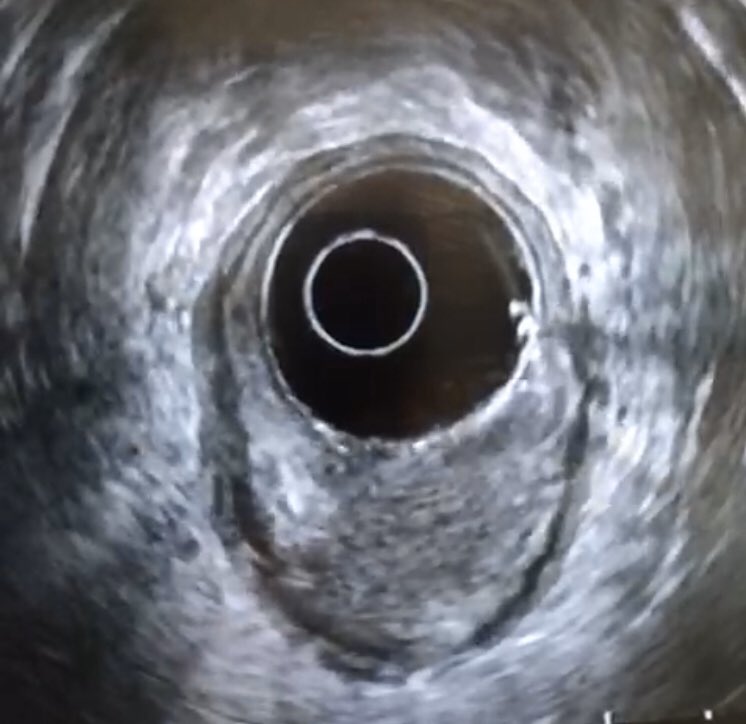

Ampullary cancer

منظار الأشعة الصوتية يظهر انسداد القناة المرارية الرئيسية بورم في فتحة اوددي. أعراض المرض صفار والتهاب في القنوات المرارية في بعض الأحيان. قد يشخص خطئا بحصوة في القناة المرارية إذا لم يتم عمل أشعة النظار الصوتية

#endoscopicultrasounds